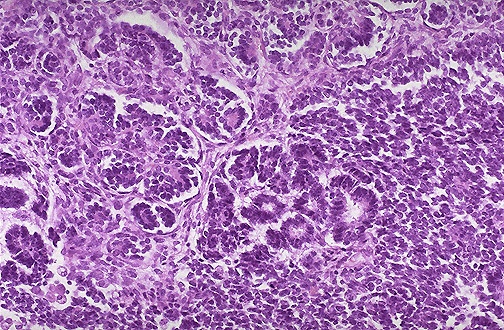

Image 4.3

At medium power microscopically in some areas, the tumor is attempting to form primitive tubules and glomeruli.